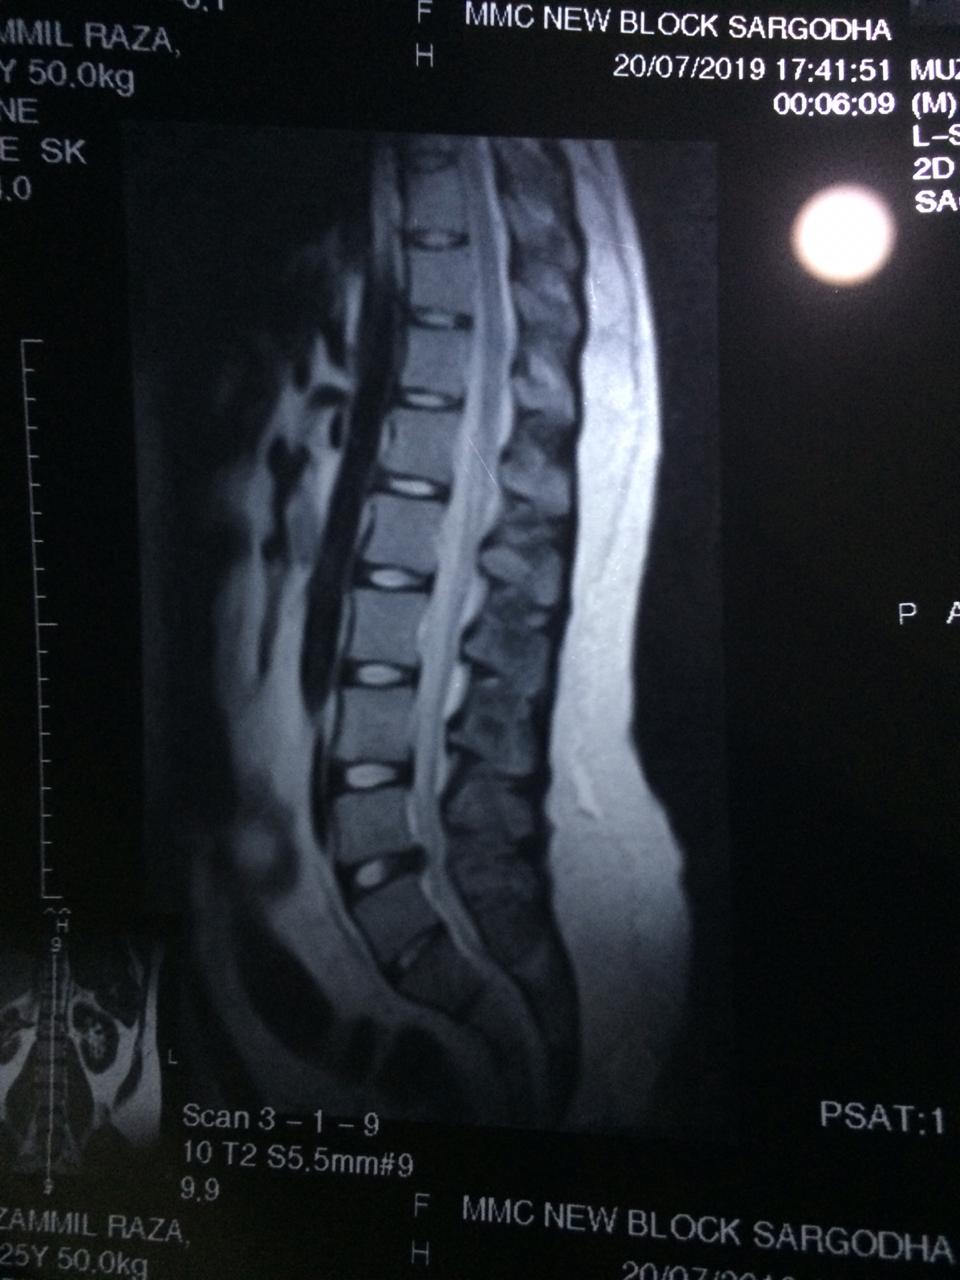

i am suffering from right leg sciatica . some disc issue in the disc between l4 and l5 which is causing compression on a nerve root. there is straightening in lLS spine aswell. this causes pain in right leg and buttock , there is stiffness in the cavity behind right knee that is not letting me keep up with the routine.

Your problem seems to be chronic ( old) .MRI also favors that you have significant compression.